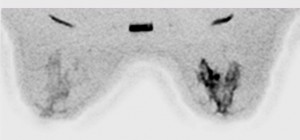

Con nuestra Nueva RM Digital podemos obtener resultados increíbles incluso en pacientes inquietos, presencia de artefactos de movimiento y Contraste de agua, grasa, en fase y fuera de fase en una sola adquisición para obtener imágenes libres de grasa.

Con adquisición de imágenes en T1W como VIBRANT/VIBRANT Flex, enhanced DWI, espectroscopia con BREASE MR, bobinas dedicadas de 16 canales de recepción y herramientas avanzadas de post-procesado para recabar toda la información que necesita para diagnosticar con total seguridad y lograr resultados positivos para sus pacientes.

Con la nueva RM digital podemos obtener imágenes de cada mama con saturación de grasa y además adquirir imágenes bilaterales en plano axial o sagital, lo que nos ha permitido mejorar de forma notable nuestro programa de diagnóstico por imagen del cáncer de mama.”